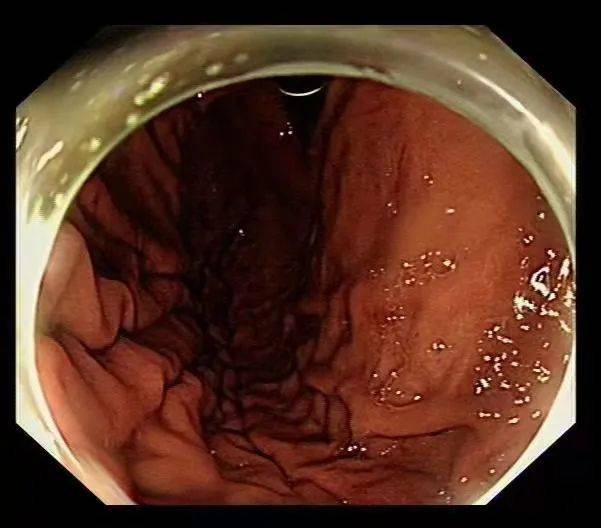

一节、二节、三节……总共有五节 , 其中四节是折断的衣架 , 一节是塑料管 。 这些从病人胃内取出的异物直径约为0.8厘米至2厘米 , 长度11-15厘米 。

最终将这几节衣架和塑料管全部取出

使病人免遭开刀之苦